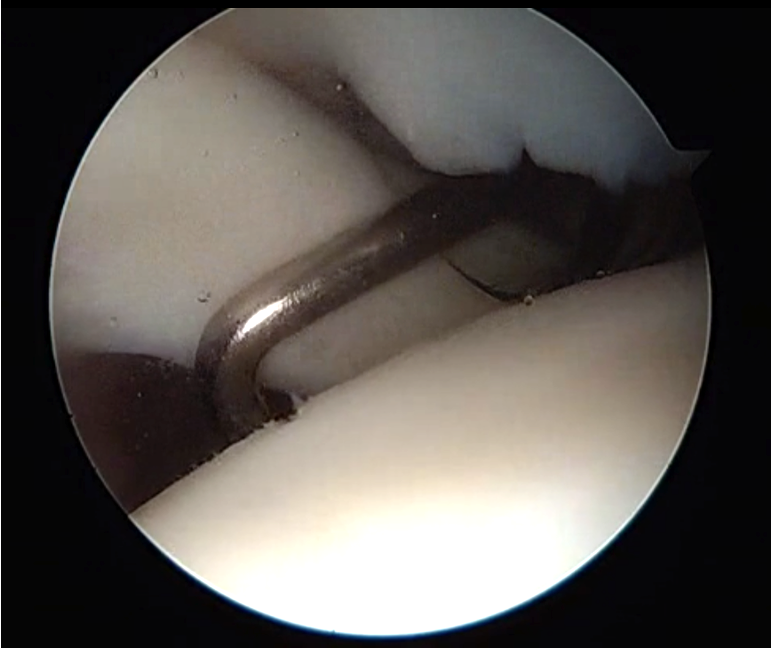

Medially dislocated biceps tendon with upper border subscapularis tear

Full thickness tear of subscapularis off insertion revealed with grasper